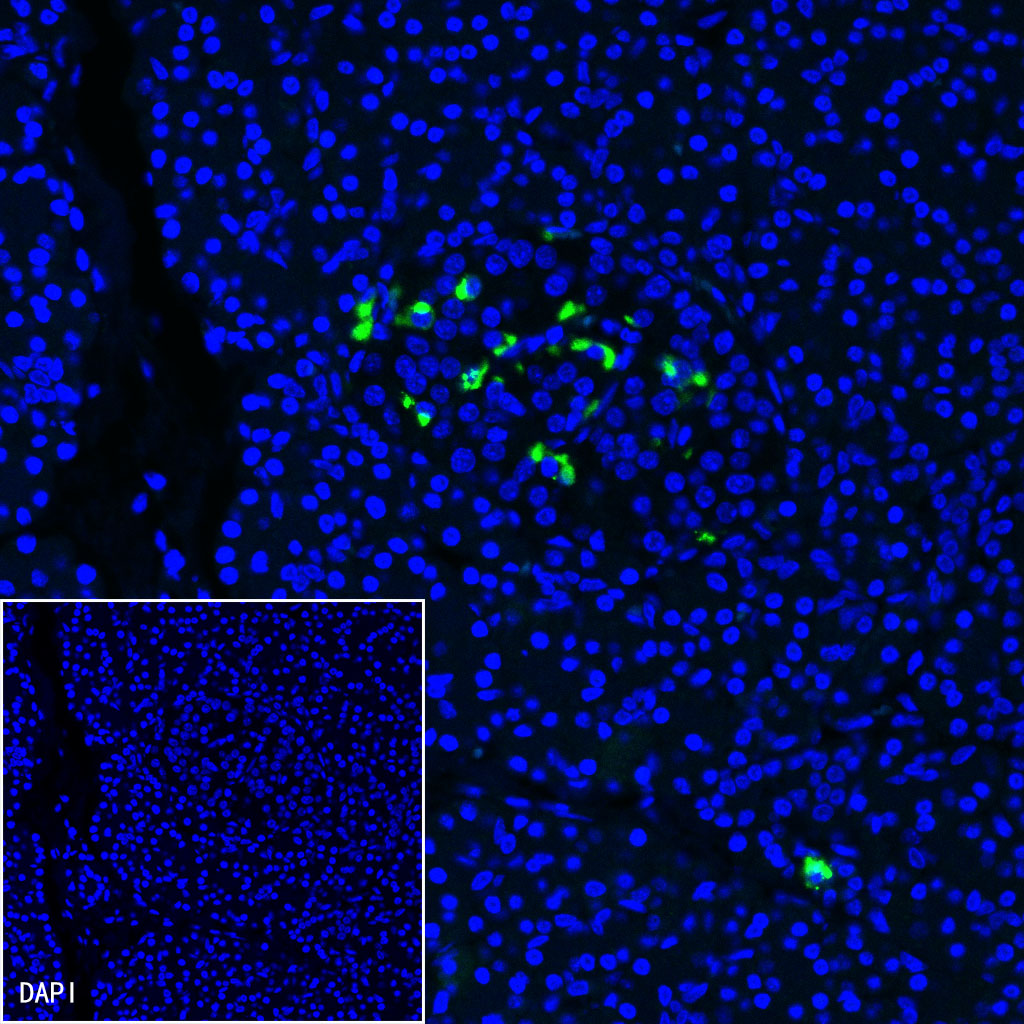

Immunofluorescence

IF shows positive staining in paraffin-embedded human pancreas. Anti-Somatostatin antibody was used at 1/250 dilution (Green) and incubated overnight at 4°C. Goat polyclonal Antibody to Rabbit IgG - H&L (Alexa Fluor® 488) was used as secondary antibody at 1/1000 dilution. Counterstained with DAPI (Blue). Heat mediated antigen retrieval with EDTA buffer pH9.0 was performed before commencing with IF staining protocol.